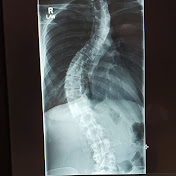

Twist Tea Episode 3 - The Power of the Bare Minimum

#scoliosis #chronicpain #spinalfusion